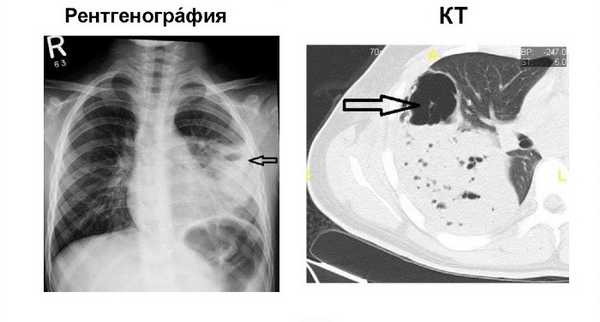

- Рентгенография легких. Основополагающую роль в установлении диагноза играют результаты рентгенологического обследования. Вместе с тем, стандартная рентгенография легких не всегда позволяет визуализировать небольшие полостные образования на фоне пневмонической инфильтрации.

- КТ грудной клетки. Поэтому при подозрении на абсцедирующую пневмонию целесообразно прибегать к проведению КТ. В случае формирования абсцесса легкого на снимках определяется толстостенное полостное образование с наличием характерного уровня жидкости и газа.

Картина, выявляемая по данным рентгенографии легких, различается в зависимости от формы бактериальной деструкции легких. В типичных случаях легочные деструкции определяются в виде полостей с горизонтальным уровнем жидкости, вокруг которых распространяется воспалительная инфильтрация легочной ткани. При плевральных осложнениях выявляется смещение тени средостения в здоровую сторону, уровень жидкости в плевральной полости, частичный или полный коллапс легкого. В этом случае целесообразно дополнение рентгенологической картины данными УЗИ плевральной полости, плевральной пункции и исследования экссудата. Бактериальную деструкцию легких требуется дифференцировать от полостной формы рака легкого, бронхогенных и эхинококковых кист, кавернозного туберкулеза. В проведении дифдиагностики, должны участвовать пульмонологи, торакальные хирурги, фтизиатры.